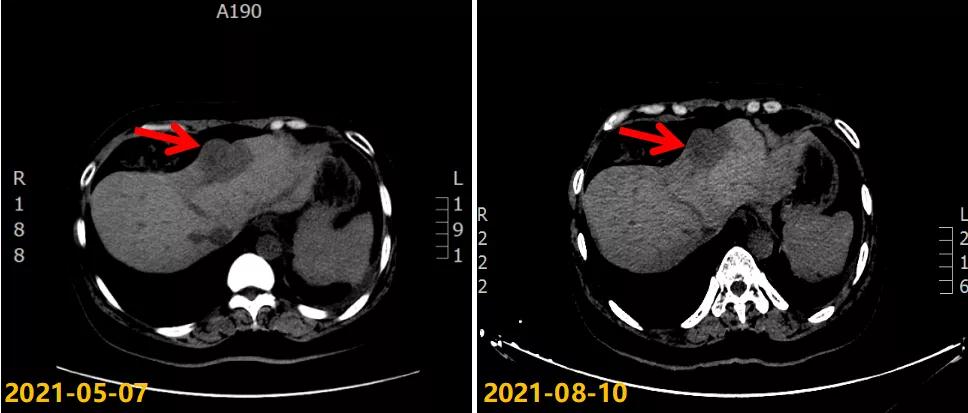

第二次病情进展:2021-05-07 CT示:左侧胸膜略增厚,同前相仿;肝脏稍低密度结节,考虑转移瘤,较前明显增大(大者4.4×3.7cm)。2021-05-08行“肝脏肿物穿刺活检”,病理结果:(肝肿物)符合转移性乳腺浸润性导管癌(组织学Ⅱ级)。免疫组化结果:ER(90%,3+),PR(85%,3+),HER2(1+),Ki-67(40%+)。

考虑患者既往辅助内分泌治疗敏感,一线内分泌治疗获益时间长,二线继续CDK4/6联合内分泌治疗,故2021-05-10起给予阿贝西利150mg po bid 联合阿那曲唑1mg po qd及戈舍瑞林3.6mg ih q4w,3月后疗效评估肝转移瘤较前稍缩小(SD),继续该方案治疗,至今PFS 6月,继续随访中。治疗期间Ⅰ-Ⅱ度骨髓抑制,对症治疗好转,无明显消化道反应,副反应较轻,可耐受。